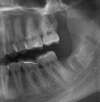

5/ Séance d'extraction de 2 dents de sagesse enclavées(en haut et en bas à gauche)... Pendant que le laboratoire de prothèse (Eric LOYAU) travaille sur les facettes selon nos consignes.